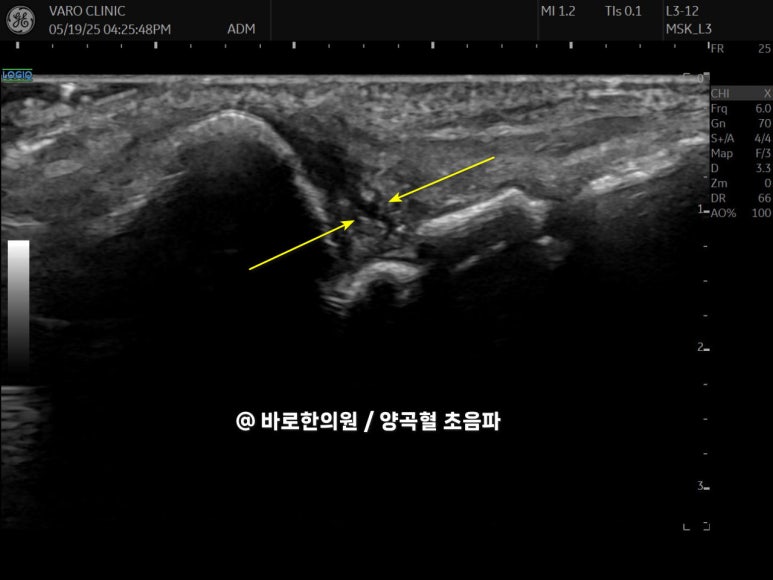

@ 바로한의원 양곡혈 초음파

정상 손목은

'쿠션'처럼 유연하게 움직이지만,

손상된 손목은

그 기능을 잃고 딱딱하게 굳어버립니다.